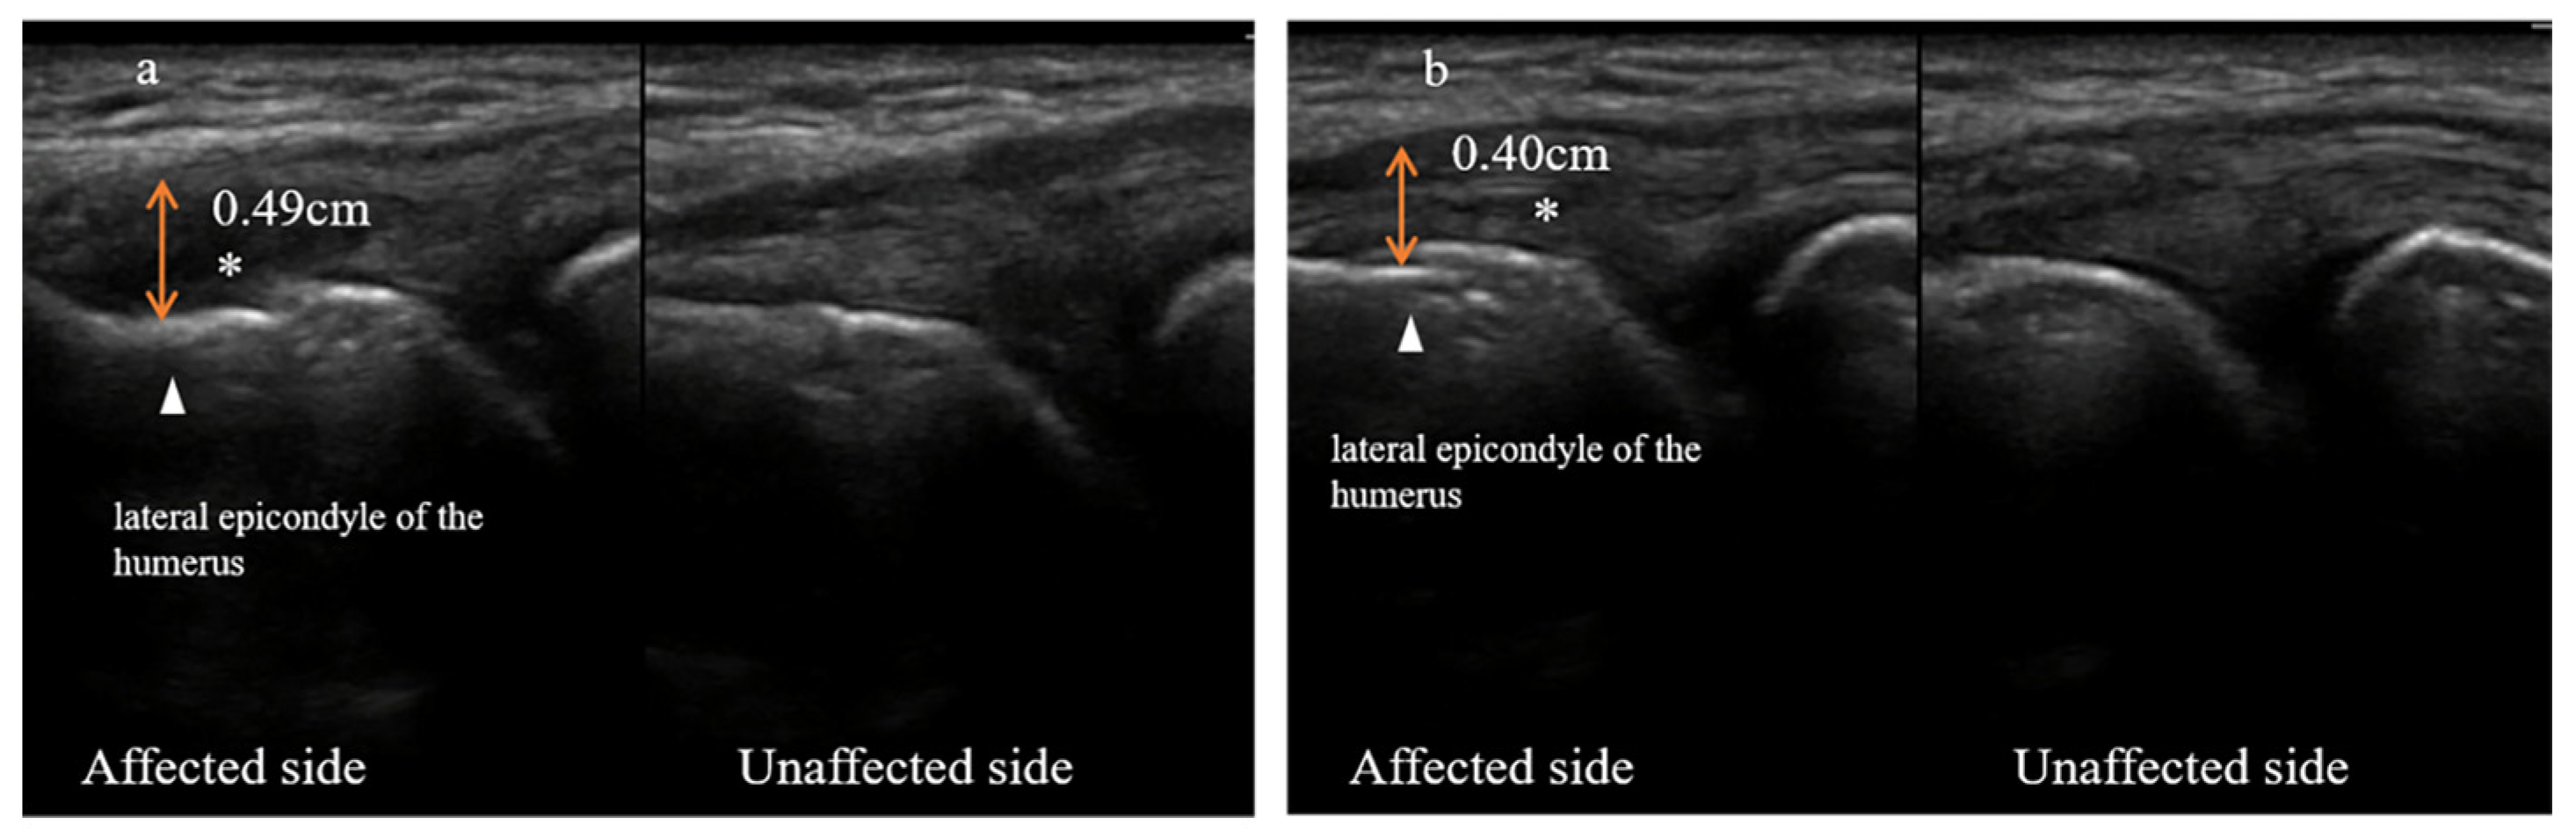

Characteristic of Ultrasonography

3.2. Ultrasonography Evaluation

3.2.1. Case One

3.2.2. Case Two